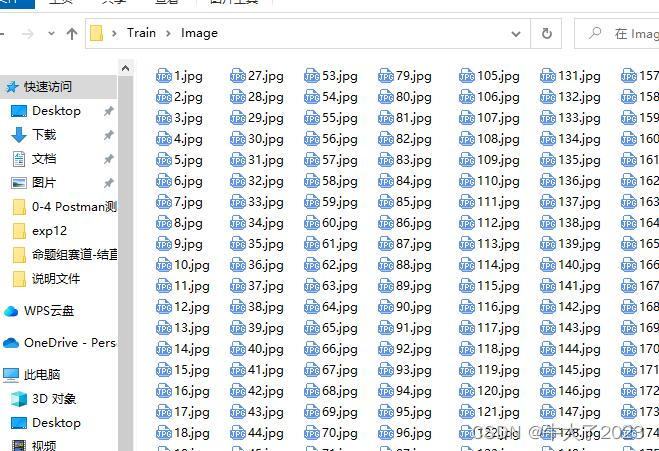

但有一些比赛和开源项目会提供图片+标注数据集供参赛选手,比如这个小比赛提供了现成的数据集,附上说明图片

训练集:28773 幅结直肠息肉内镜图像(原始图像、标签和 Readme 文件)。网盘链接如下:链接: https://pan.baidu.com/s/1n08y04DokW5LyF0t7tMIog提取码: tmkn